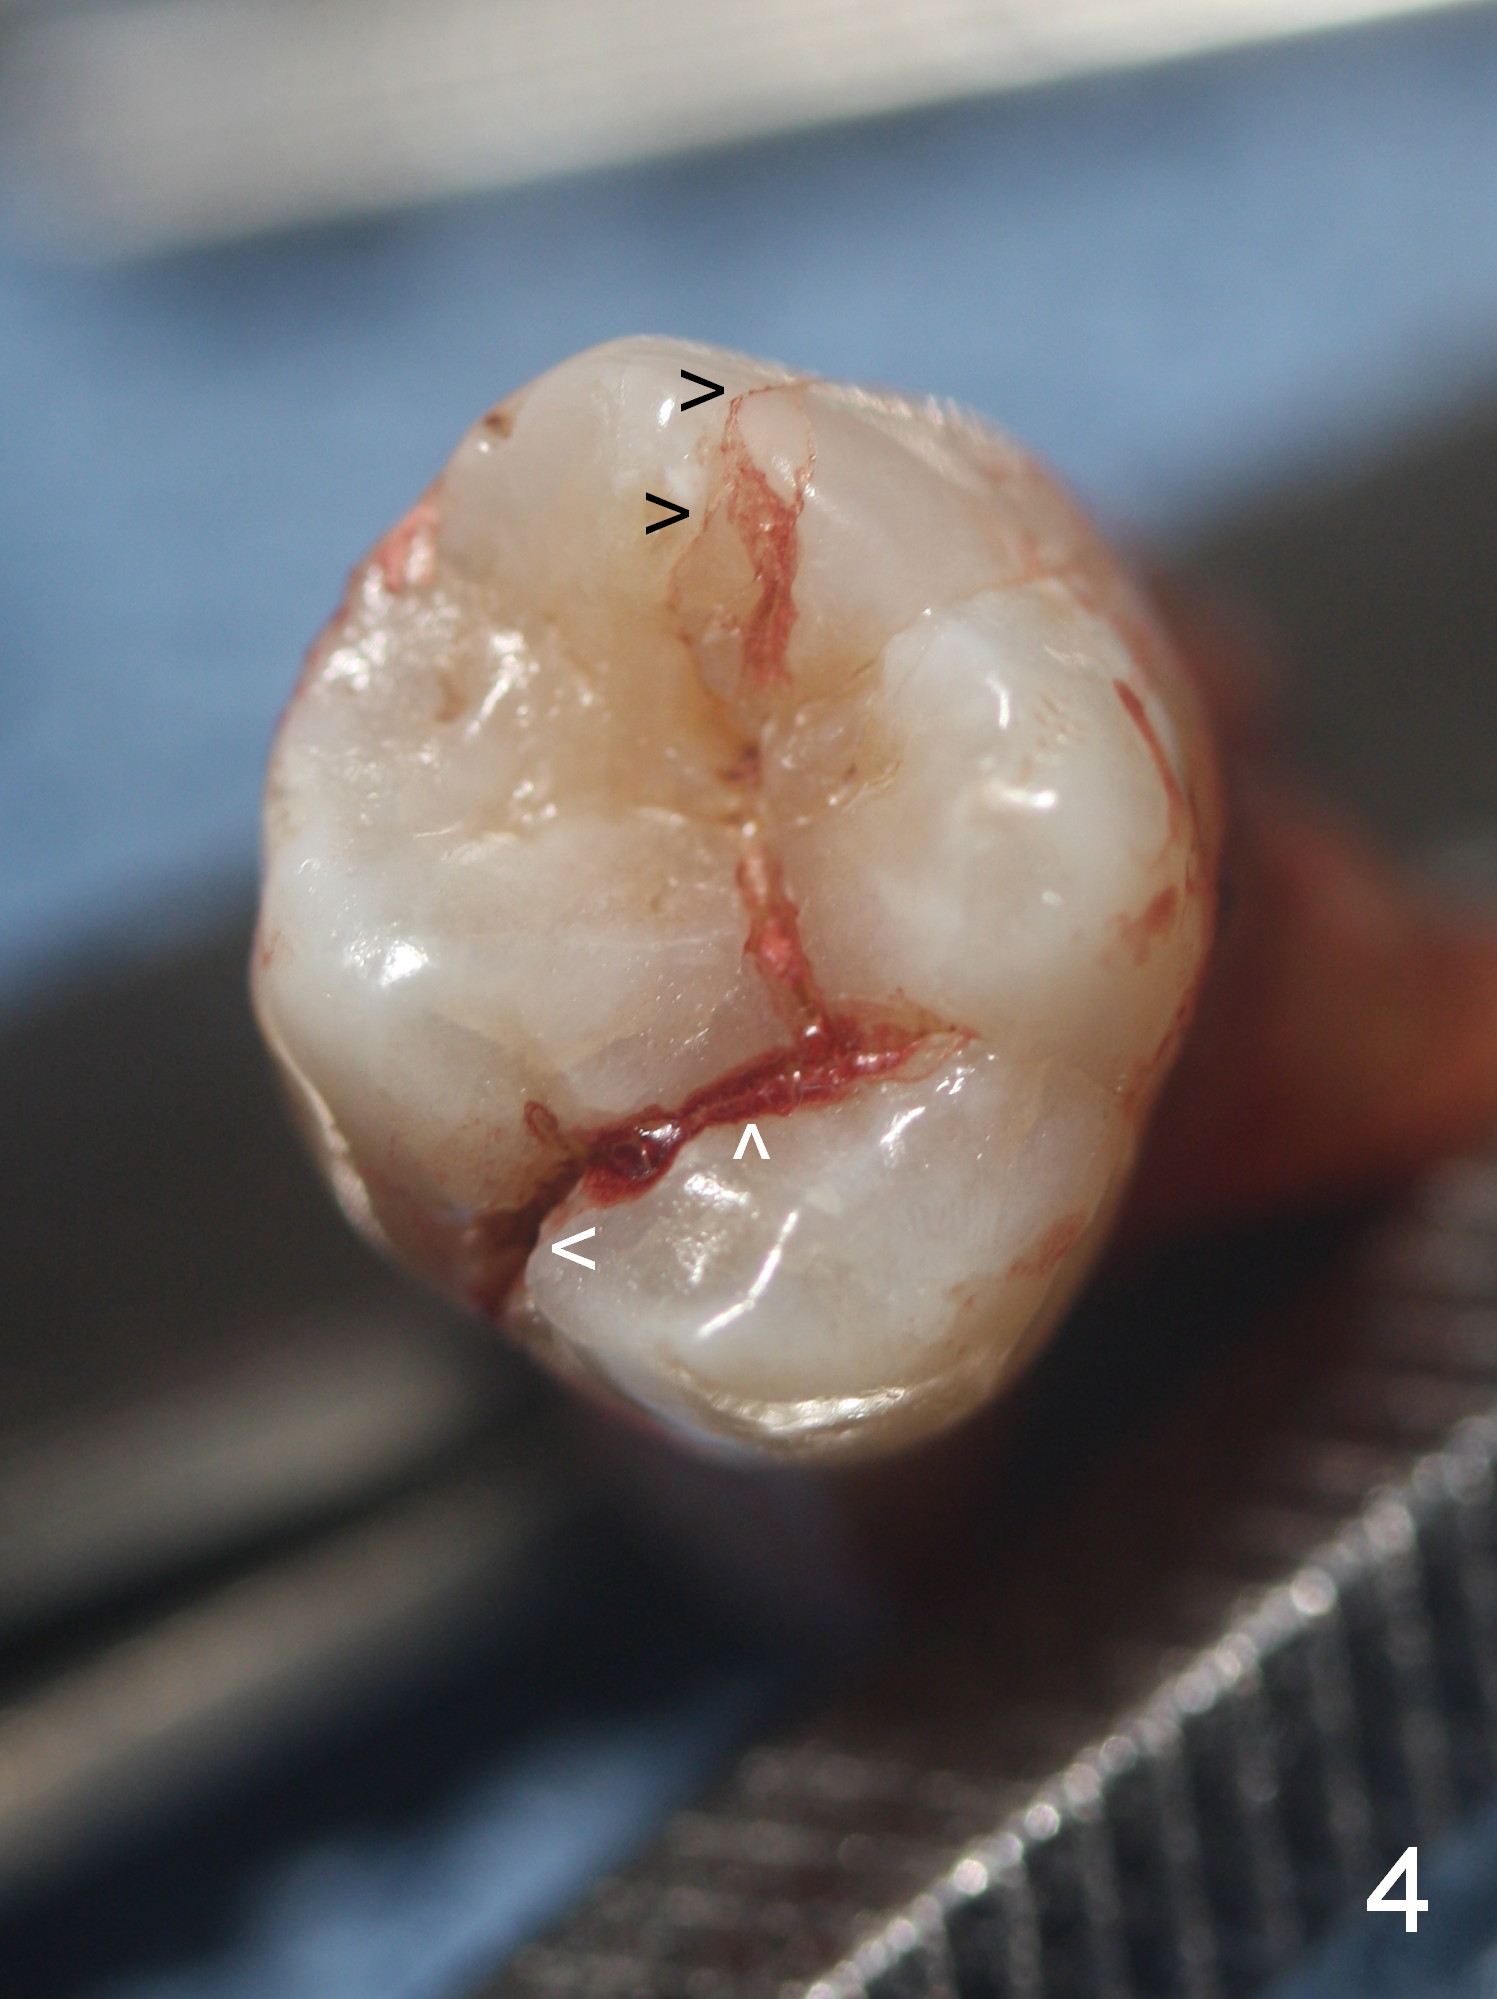

When the tooth is extracted, the lingual crack line (Fig.4 white <) is contiguous with the mesiobuccal one (black >). The latter corresponds to the white arrowheads in Fig.2. In all the crack line is extensive. The buccal and palatal plates are defective coronally. The large granulation tissue in the furca (Fig.5 *) suggests bone loss in the crestal septum. Most surprising is a crack line in the distal surface of the tooth #13 (Fig.6 ^) and in the mesial surface of #15 (Fig.7). Night guard will be fabricated after an implant crown is cemented at #14.